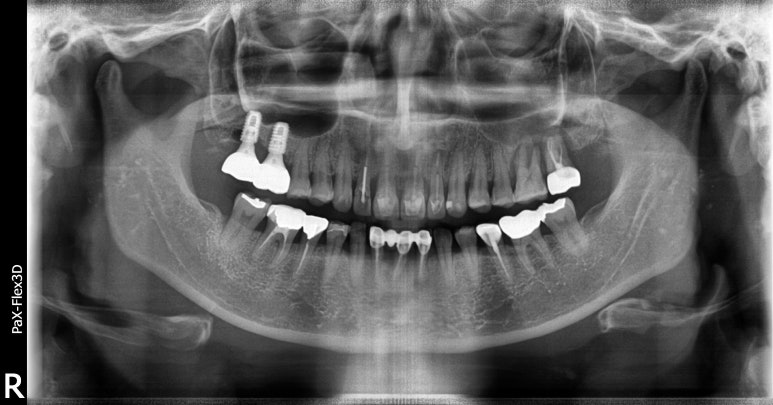

상악동거상술을 동반한 임플란트 치료 전

2022-08-23

상악동거상술을 동반한 임플란트 치료 전후

(전) 2022-08-23 (후) 2023-07-25

이번 환자분의 경우 사진상 오른쪽(실제 왼쪽) 맨끝 어금니 2개를 임플란트로 치료하신 케이스인데요.

뼈이식 6개월 후에 뼈가 단단해지는지 지켜보고 임플란트를 식립하기로 했습니다. (지연식립)

최초 뼈이식을 22년 8월 말에 진행하셨고, 임플란트 수술은 23년 2월 말에 진행하셨으니 딱 6개월 후에 임플란트를 식립하게 되신 것이죠.

임플란트를 식립하고 4개월 후에 보철물(크라운)을 올리는 계획으로 진행했는데,

3개월 후 수치 측정 결과 아직은 뼈가 단단하게 굳지 않았다고 판단해 한달 더 기다린 후 7월에 보철물을 세팅하게 되었습니다.

최종적으로 거의 1년 정도 소요되었다고 보시면 될 것 같습니다.

만약 이렇게 임플란트+뼈이식+상악동거상술까지 동반하게 된다면 비용은

임플란트 개당 비용에 뼈이식 비용 30만원, 상악동거상술 비용 50100만원이 별도로 총 150200만원 정도 비용이 발생하게 됩니다.